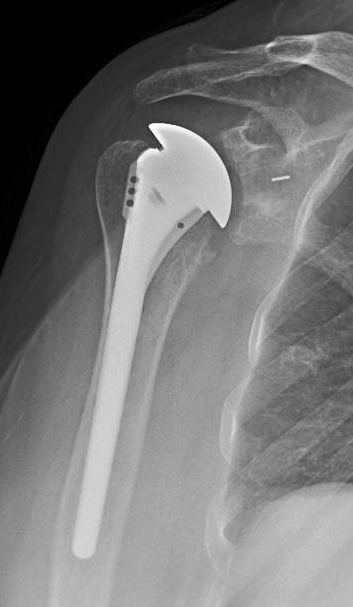

Her 6 week post operative films are shown below. Note the fixation of the humeral stem with impaction autograft and the absence of radiolucent lines around the glenoid fixation pegs.